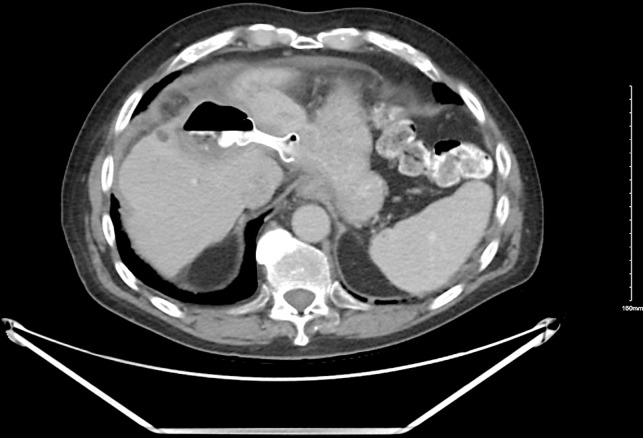

Introduction: Hepatic cysts, commonly discovered incidentally, can become symptomatic due to complications like infection, rupture, or mass effect. Traditional management options include percutaneous drainage, open surgical or laparoscopic deroofing, and liver resection. We present a case series of 3 patients with complex fluid collections in the liver managed by endoscopic ultrasound (EUS)-guided drainage using lumen-apposing metal stent (LAMS) placement. While reports exist from other countries, our study contributes a series of cases from the USA.

Case presentation: Three patients, average age 75 years (two men, one woman), underwent EUS-guided drainage using LAMS for an infected liver cyst, infected liver hematoma within a hepatocellular carcinoma lesion, and a symptomatic simple liver cyst, respectively. All the hepatic fluid collections were in the left hepatic lobe and had an average diameter of 11 centimeters (cm). Only the female patient with a symptomatic cyst had prior percutaneous drainage. Successful LAMS placement was achieved in all cases. Clinical success, defined as cyst resolution or significant size reduction, was observed in all patients. The superinfected liver cyst showed complete resolution, yet the stent remained in place as the patient transitioned to hospice and subsequently passed away. In the case of the superinfected liver hematoma, the stent was removed after 2 months. No recurrence was observed in follow-up imaging 8 months later, and the patient passed away. The symptomatic simple liver cyst patient had the stent removed 15 months later, with no recurrence in imaging 11 months of post-stent removal.

Conclusion: EUS-guided LAMS placement emerges as a less invasive and viable option for treating symptomatic and/or infected hepatic fluid collections compared to surgery or percutaneous drainage. While it may be a preferable choice in institutions with the requisite expertise, further studies are essential to establish its definitive role as a first-line intervention.